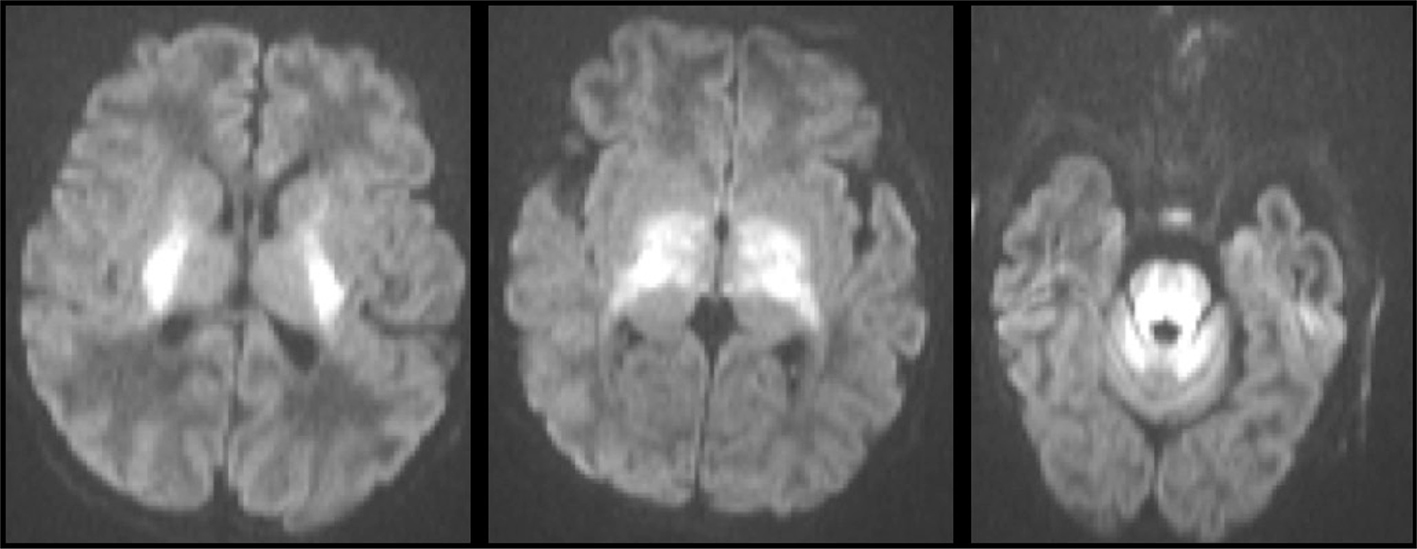

STROKE MIMICS

Clinically diagnosing stroke in neonates can be difficult due to the non-localizing and nonspecific signs of stroke, such as lateralized weakness after seizure or ataxia, are often overlooked (117). Other neurologic diagnoses can have a similar presentation, including congenital and acquired metabolic disorders, hypoglycemia, in addition to epilepsy, intracranial infection or inflammation, focal lesions, and drug toxicity (Figures 11 and 12) (118, 119).

Fig 11

Figure 11. A 20-day-old boy with classic-type of maple syrup urine disease (MSUD). Axial DWI images showing symmetric pattern of acute restricted diffusion in the basal ganglia, thalami, brainstem, characteristic of exacerbation of MSUD. Case courtesy of Dr. Tamara Feygin, Department of Radiology, Children’s Hospital of Philadelphia.

Fig 12

Figure 12. A three-weeks-old girl with seizures and hypoglycemia. Axial CT (A) and axial DWI (B), and ADC (C) MR images show low density and loss of gray-white matter differentiation in the posterior half of the cerebral hemispheres on CT and reduced diffusion on MRI. The extent of the signal abnormality is much greater than usually seen with watershed infarction in the border zone between the MCA and PCA. Case courtesy of Dr. Tamara Feygin, Department of Radiology, Children’s Hospital of Philadelphia.